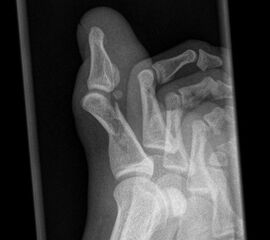

Besondere Bemerkungen zum Beispielbild:

• Großzehe dp bei Grundgliedfraktur mit diaphysäre Trümmerzone.

• Sesamoid im Ansatzbereich der Flexor hallucis longus Sehne.

• Großzehe schräg bei Grundgliedfraktur mit diaphysäre Trümmerzone.

• Die Dislokation ist in der Schrägaufnahme gut erkennbar.